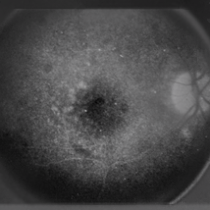

Furthermore, generated images from FA images are presented in Fig. 6 and Fig. 7. Results in the images are nearly identical to the original images, because original networks are applied to stylize color images. However, six generated images contain more concise features than the original ones, which helps ophthalmologists make better judgments. Therefore, this style transferring networks can fulfill edge sharpening and enhancement of contrast. No matter which kinds of images are generated, advanced features in new disease images still exist. Furthermore, analyses of image performance by EyeNet and CAMs for prediction are presented in a later section.

Figure 6: Three FA fundus images with symptom of drusen and corresponding generated images. (a), (b), (c) Original images. (d), (e), (f) Generated images.